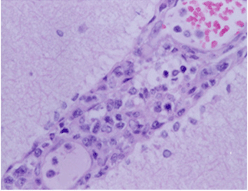

주요임상증상